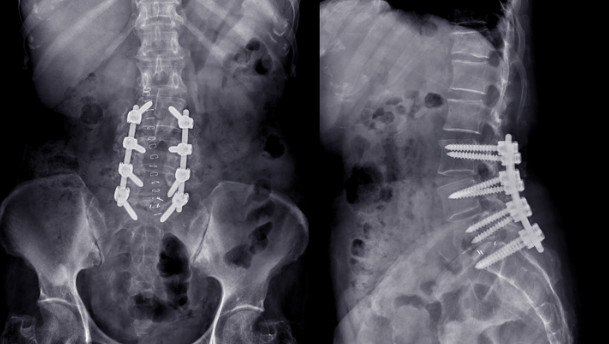

척추 수술후 통증 증후군 (척추 수술후 실패 증후군)은 성공적인 수술임에도 불구하고 예상치 못한 허리통증과 다리저림등의 신경증상이 잔존하는 경우를 가리킵니다.

디스크의 재발, 수술인접부위의 변화, 신경유착등의 원인이외에도 불충분한 신경감압, 고정 기구의 이상등 다양한 이유가 존재합니다.